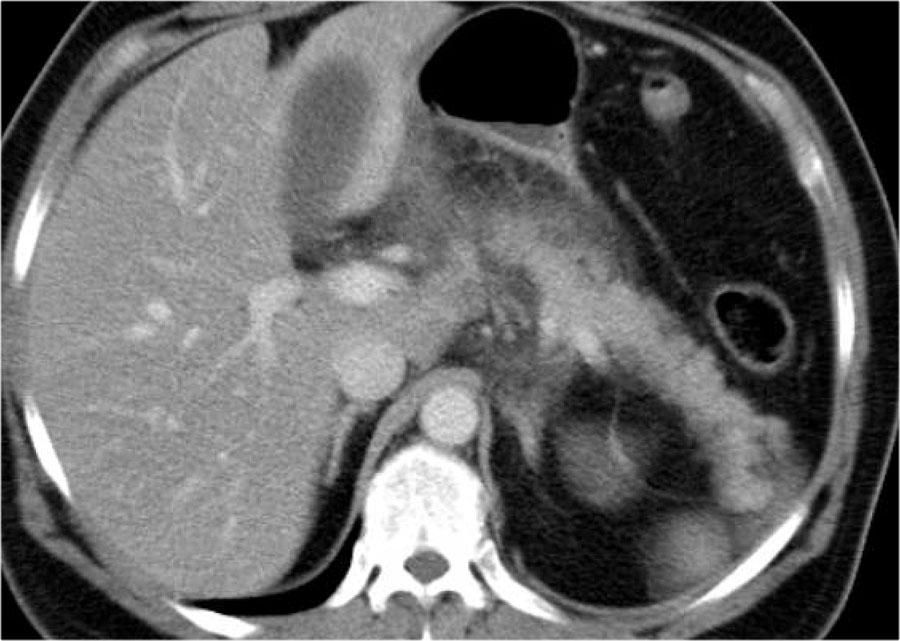

Hình CT cho thấy viêm tụy hoại tử cấp tính.

Thân và đuôi tụy không ngấm thuốc.

Đầu tụy ngấm thuốc bình thường (mũi tên).

Hơn 50% nhu mô tụy bị hoại tử và có ít nhất hai ổ dịch.

CTSI: 4 + 6 = 10 điểm.